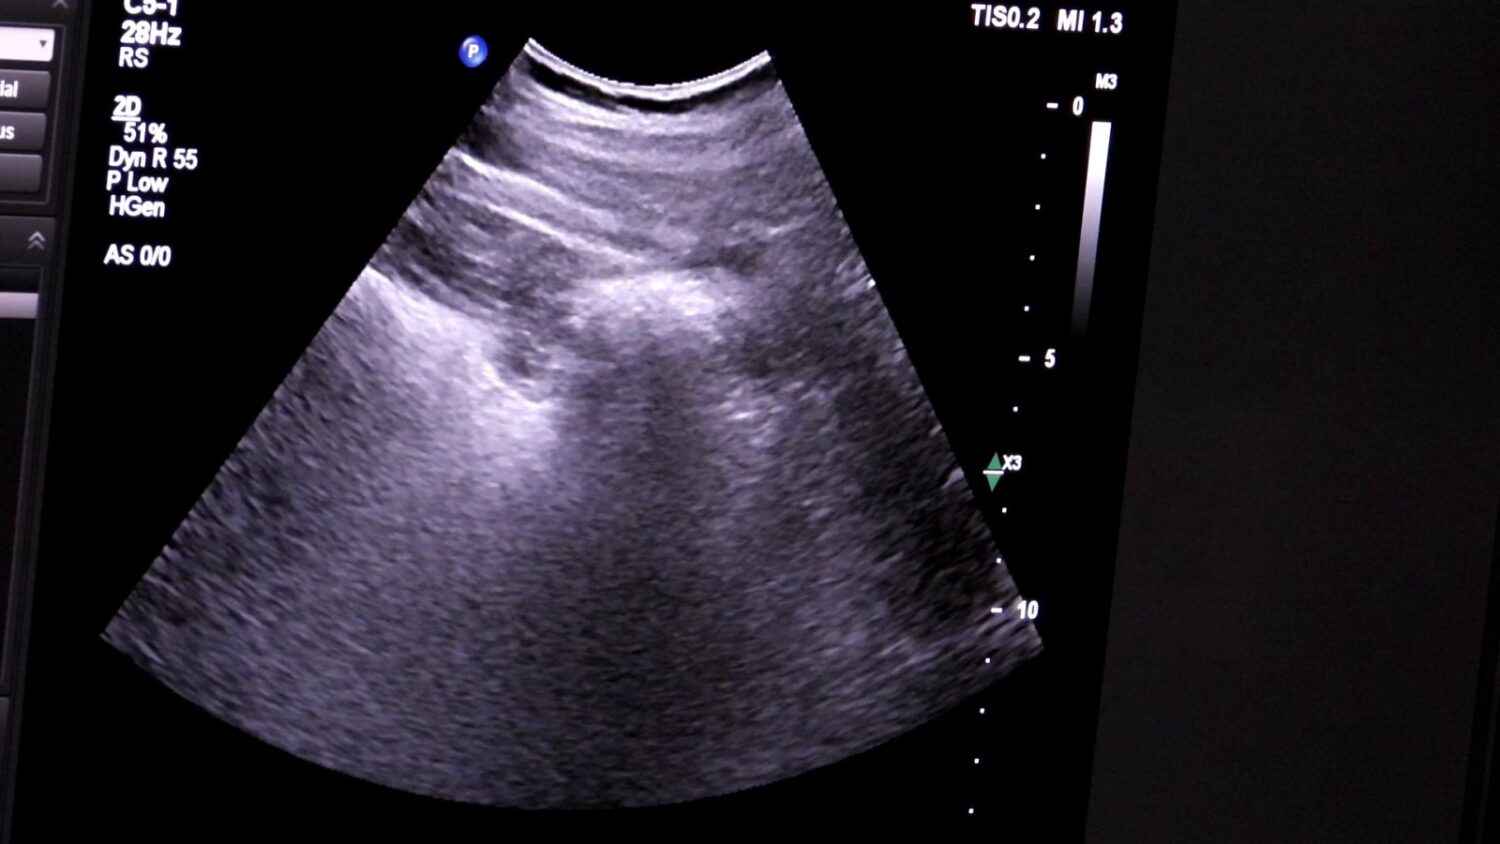

Tokom tri sedmice pregleda obavljenih u Edukacijskom centru KBZ-a, detaljnim pregledima je pristupilo 200 građana. Ultrazvuk abdomena je brz, bezbolan i siguran način da se provjeri stanje unutrašnjih organa, poput jetre, bubrega, gušterače i žučne kese.

Ultrazvuk abdomena je jednostavna, bezbolna i sigurna metoda pregleda pomoću koje možemo pregledati organe i strukture koji se nalaze unutar trbušne šupljine. Ovaj pregled igra važnu ulogu u ranom otkrivanju promjena koje mogu dovesti do narušavanja zdravlja i razvoja bolesti.